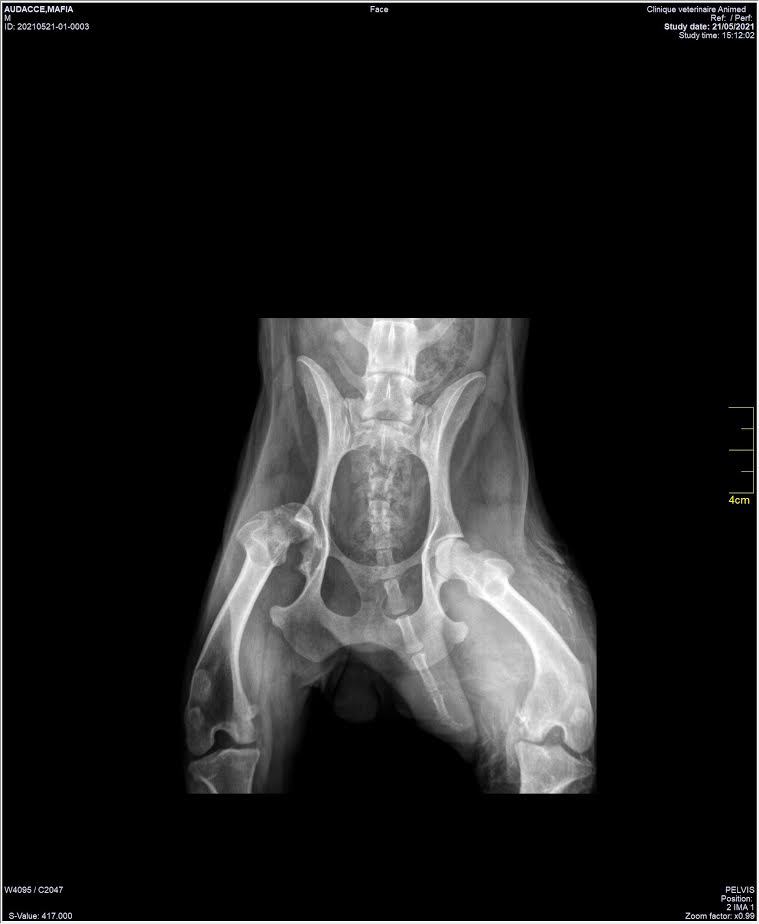

Avant que je ne puisse profiter de ma nouvelle vie, il va quand même falloir faire quelques ajustements : le spécialiste en orthopédie a dit qu'il fallait m'opérer de la hanche qui doit être déboitée depuis plusieurs années déjà et m'empêche de poser une patte arrière. C'est une chirurgie couteuse et une longue rééducation mais cela me permettra de pouvoir vivre le reste de ma vie chouchoutée et sans douleur.